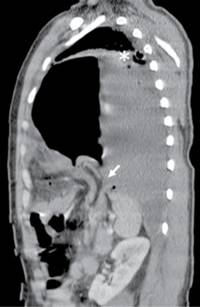

Figura 3: Corte sagital de TC en fase contrastada a nivel de la línea medio-clavicular izquierda donde se observa defecto herniario de músculo diafragmático izquierdo (flecha) con protrusión de estómago y grasa mesentérica hacia cavidad torácica condicionando atelectasia parcial de pulmón ipsilateral(*).